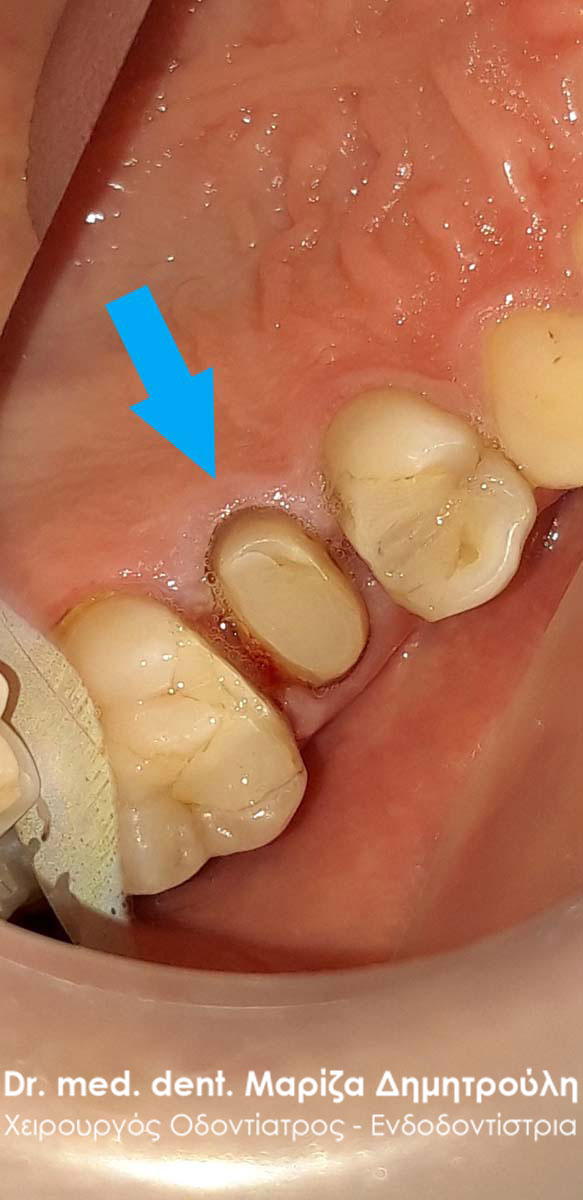

Ο ασθενής είχε ολοκληρώσει την απονεύρωση δοντιού στο δεύτερο κάτω αριστερό προγόμφιο χωρίς όμως να προχωρήσει στην προστασία του δοντιού με θήκη. Στο συγκεκριμένο περιστατικό, σύμφωνα πάντα με τα λεγόμενα του ασθενή, είχε προταθεί η αποκατάσταση του δοντιού με στεφάνη, εφόσον έλλειπε μεγάλο τμήμα του δοντιού και ήταν επικίνδυνο να σπάσει. Πράγματι μετά από καιρό το δόντι έσπασε και απέμεινε μόνο η ρίζα του δοντιού. Ο ασθενής επιθυμούσε τη διατήρηση του δοντιού στο στόμα του παρόλο που του είχε προταθεί η εξαγωγή του συγκεκριμένου δοντιού.

Μετά την κλινική και ακτινογραφική εξέταση διαπιστώθηκε οτι το δόντι θα μπορούσε να σωθεί δεδομένου οτι θα τοποθετούταν στη ρίζα του δοντιού ειδικός άξονας και στη συνέχεια το δόντι θα προστατευόταν με θήκη δοντιού.

Πράγματι το δόντι προετοιμάστηκε κατάλληλα και τοποθετήθηκε στο εσωτερικό της ρίζας λευκός άξονας υαλονημάτων. Ακολούθησε η ανασύσταση της μύλης του δοντιού και ο εκτροχισμός του ψευδοκολοβώματος. Στη συνέχεια λήφθηκαν αποτυπώματα και στάλθηκαν στον οδοντοτεχνίτη για την κατασκευή της θήκης του δοντιού.

ΠΡΙΝ